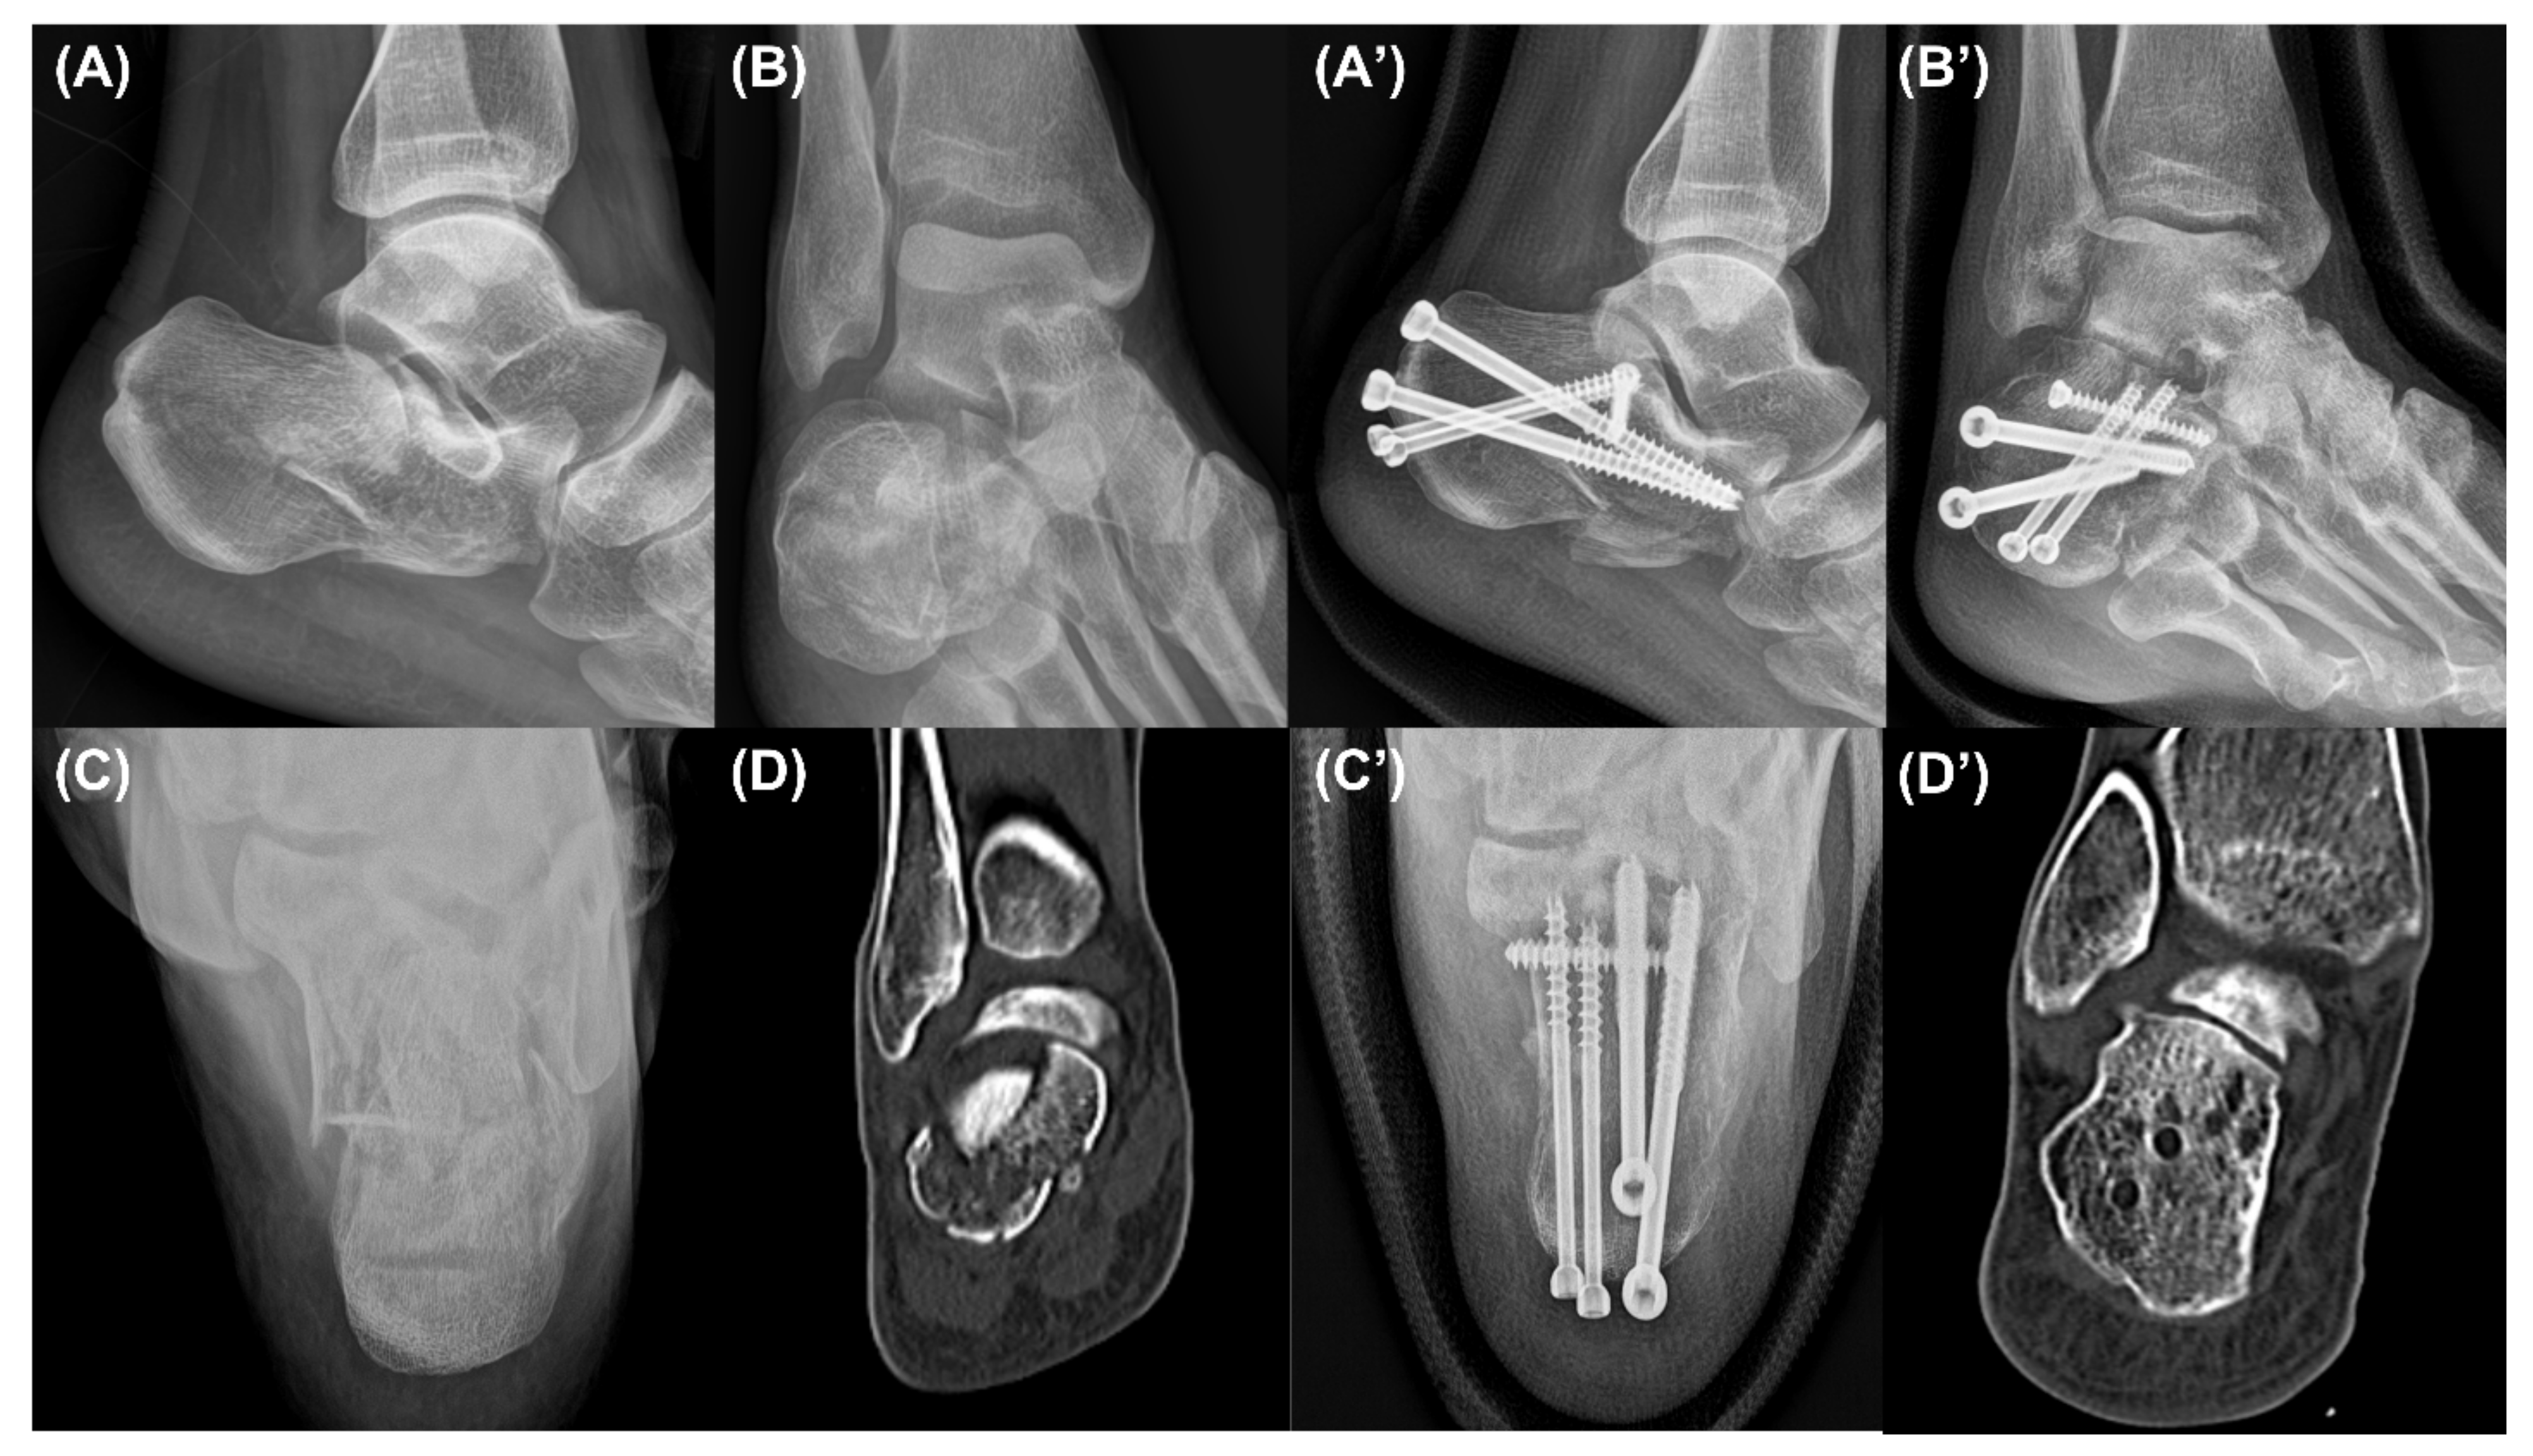

2.2. Surgical Technique